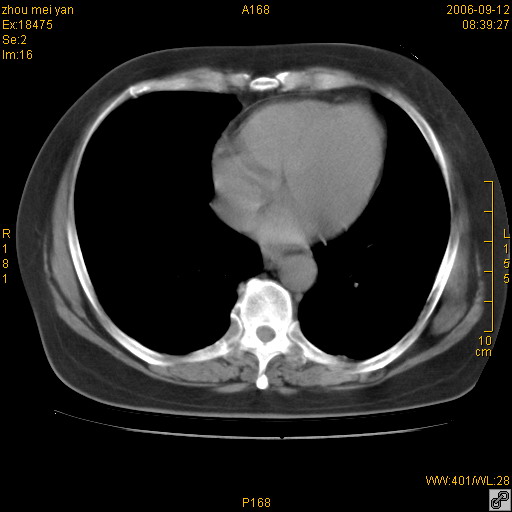

患者、女、55岁。因心率失常住院检查ct发现胸部多发结节。腹部b超肝、胆、胰、脾、肾、子宫附件未见异常。无结核病史,无粉尘接触史。请大家来会诊。谢谢!

病变位于胸膜,多发结节,边界清楚,内见小结节状钙化。其它未见异常。

双侧胸膜多发结节,形态不规则,边缘较清楚,每一个结节中心似乎都有钙化点的特征,与胸膜广基相切。临床无结核病史,无粉尘接触史。

胸膜间皮瘤可能性大。在气管隆突前可见一肿大淋巴结影。

影像表现十分有特点:双侧肋胸膜及膈胸膜广泛散在分布大小在2至6mm左右,较大病灶中心可见钙化。